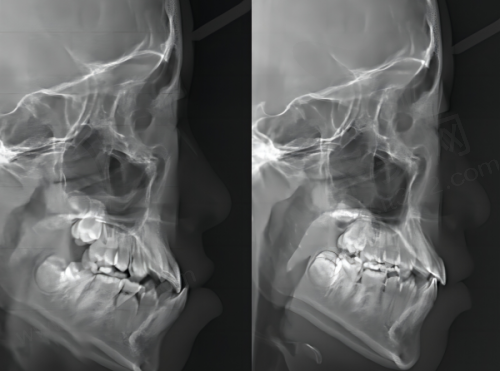

近年来,医院在口腔数字化临床应用等重点领域实现关键技术突破,开展的新技术如基于数字化导板的复杂阻生牙、多生牙拔除、牙颌面畸形综合矫治技术、儿童舒适化口腔治疗等,有效填补省内乃至国内外空白。就拿基于数字化导板的复杂阻生牙、多生牙拔除来说,以前拔除这些牙齿可能就像在黑暗中摸索,而现在有了数字化导板,就像是有了一个精细的地图,医生可以更加正确地进行操作,大大提高了手术的成功几率和安心性。